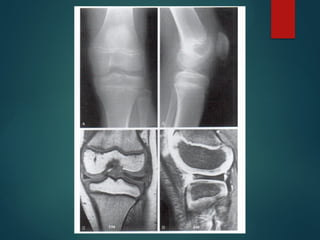

Rx

 En las rx laterales =

desplazamiento parcial

(subluxación) o luxación

completa de la tibia sobre el

fémur

 En las rx AP = subluxación lateral

o rotatoria asociada con

deformidad en valgo

 Hipoplasia o ausencia de los

centros de osificación

 TAC y RMN en casos severos y

planificación preoperatoria